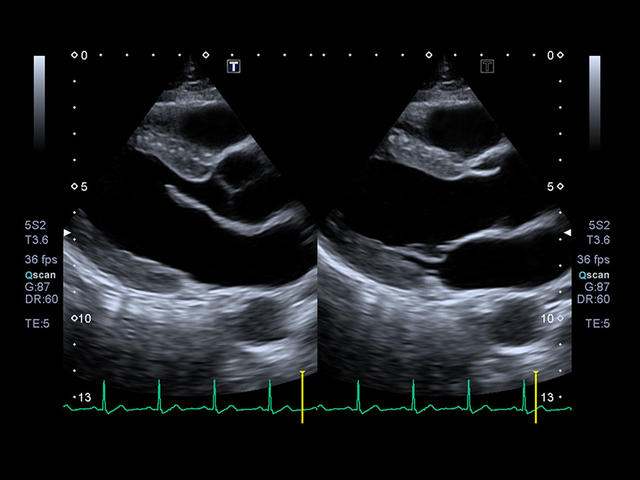

- Кардиология

- Превосходное качество изображений и максимальная детализация. Четкое прорисовывание границ и повышенная однородность изображения позволяют без сомнений устанавливать точный диагноз.

- Оптимизация 2D изображения – QuickScan.

- Оценка глобальной и локальной сократимости ЛЖ сердца в 2D: 2D Wall Motion Tracking

- Стресс эхокардиография: Stress Echo